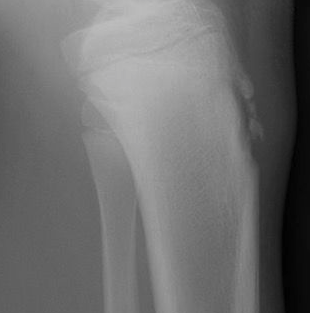

Maladie d’Osgood-Schlatter

- Microtrauma sur la TTA (insertion tibiale du tendon patellaire)

- Ne pas confondre avec un noyau d’ossification normal de la TTA

- Ne pas confondre avec une lésion traumatique d’avulsion aigue (le contexte aide)